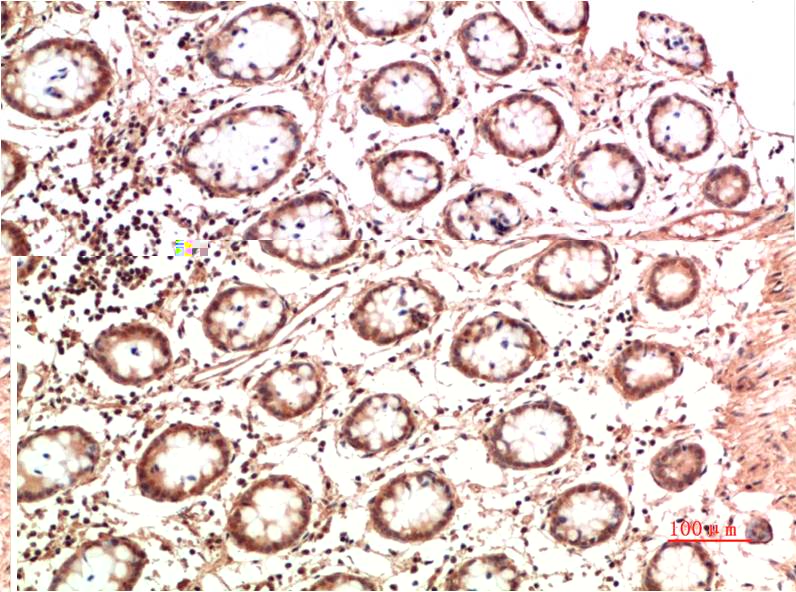

c-Jun Mouse Monoclonal Antibody(4G10)

Applications :IHC

| Recommended dilutions: | IHC 1:100-200 |

| Specificity: | The c-Jun Mouse Monoclonal Antibody can detects endogenous c-Jun proteins. |